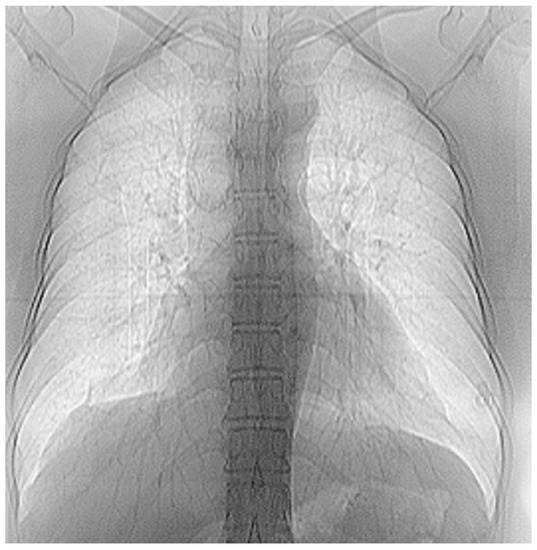

Several patients with a preliminary diagnosis of COVID-19 were tested using CT imaging with the contrast substance OMNIPAQUE 350. The pulmonary CT images obtained for each patient, along with their detailed fractal analysis, are presented in Figure 1, below.

Figure 1. (a) The CT scan image of a 69-year-old patient who underwent a chest CT examination due to suspicion of COVID-19 in the lungs. (b) A schematic representation of the pre-processing phases of the patient’s CT image (2D), which was resampled to an isomorphic resolution. The indices 5, 14, and 16 represent the numbers of the slices in order.